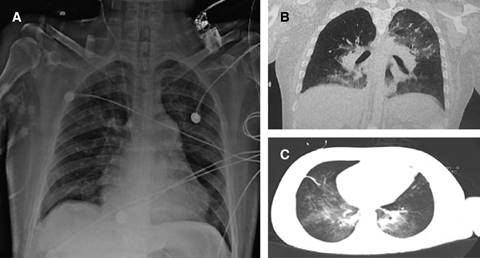

Figura 1: A) Radiografía simple de tórax. B y C) Angiotomografía de tórax. Observe como la radiografía simple puede no mostrar hallazgos significativos, comparado con la TAC que muestra signos compatibles con hemorragia alveolar.

La fibrobroncoscopia permite identificar los casos con alta sospecha cuando la hemoptisis no es evidente. En el lavado broncoalveolar se identifican macrófagos cargados de hemosiderina a partir de las 48 horas de iniciado el cuadro clínico, lo que confirma el diagnóstico; no obstante, hay que considerar que éstos también pueden presentarse en casos de procesos infecciosos (citomegalovirus, Legionella e incluso Candida albicans), o exacerbaciones de enfermedades pulmonares intersticiales. Los estudios radiográficos, particularmente los de alta resolución, aportan información clave para el diagnóstico (tomografía computada de tórax), la radiografía simple de tórax puede mostrar hallazgos atípicos con áreas focales asimétricas bilaterales de consolidación u opacidades en vidrio deslustrado; las radiografías de tórax de los pacientes con lupus y hemorragia alveolar difusa también pueden tener una apariencia normal o casi normal (nótese la Figura 1 que muestra la radiografía de tórax del caso descrito).